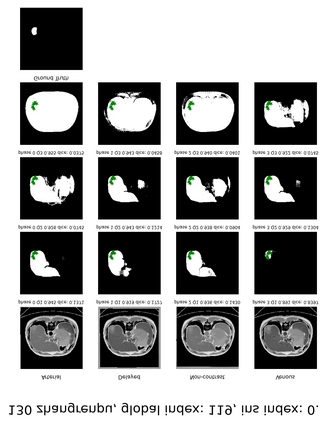

Learning to segmentation without large-scale samples is an inherent capability of human. Recently, Segment Anything Model (SAM) performs the significant zero-shot image segmentation, attracting considerable attention from the computer vision community. Here, we investigate the capability of SAM for medical image analysis, especially for multi-phase liver tumor segmentation (MPLiTS), in terms of prompts, data resolution, phases. Experimental results demonstrate that there might be a large gap between SAM and expected performance. Fortunately, the qualitative results show that SAM is a powerful annotation tool for the community of interactive medical image segmentation.